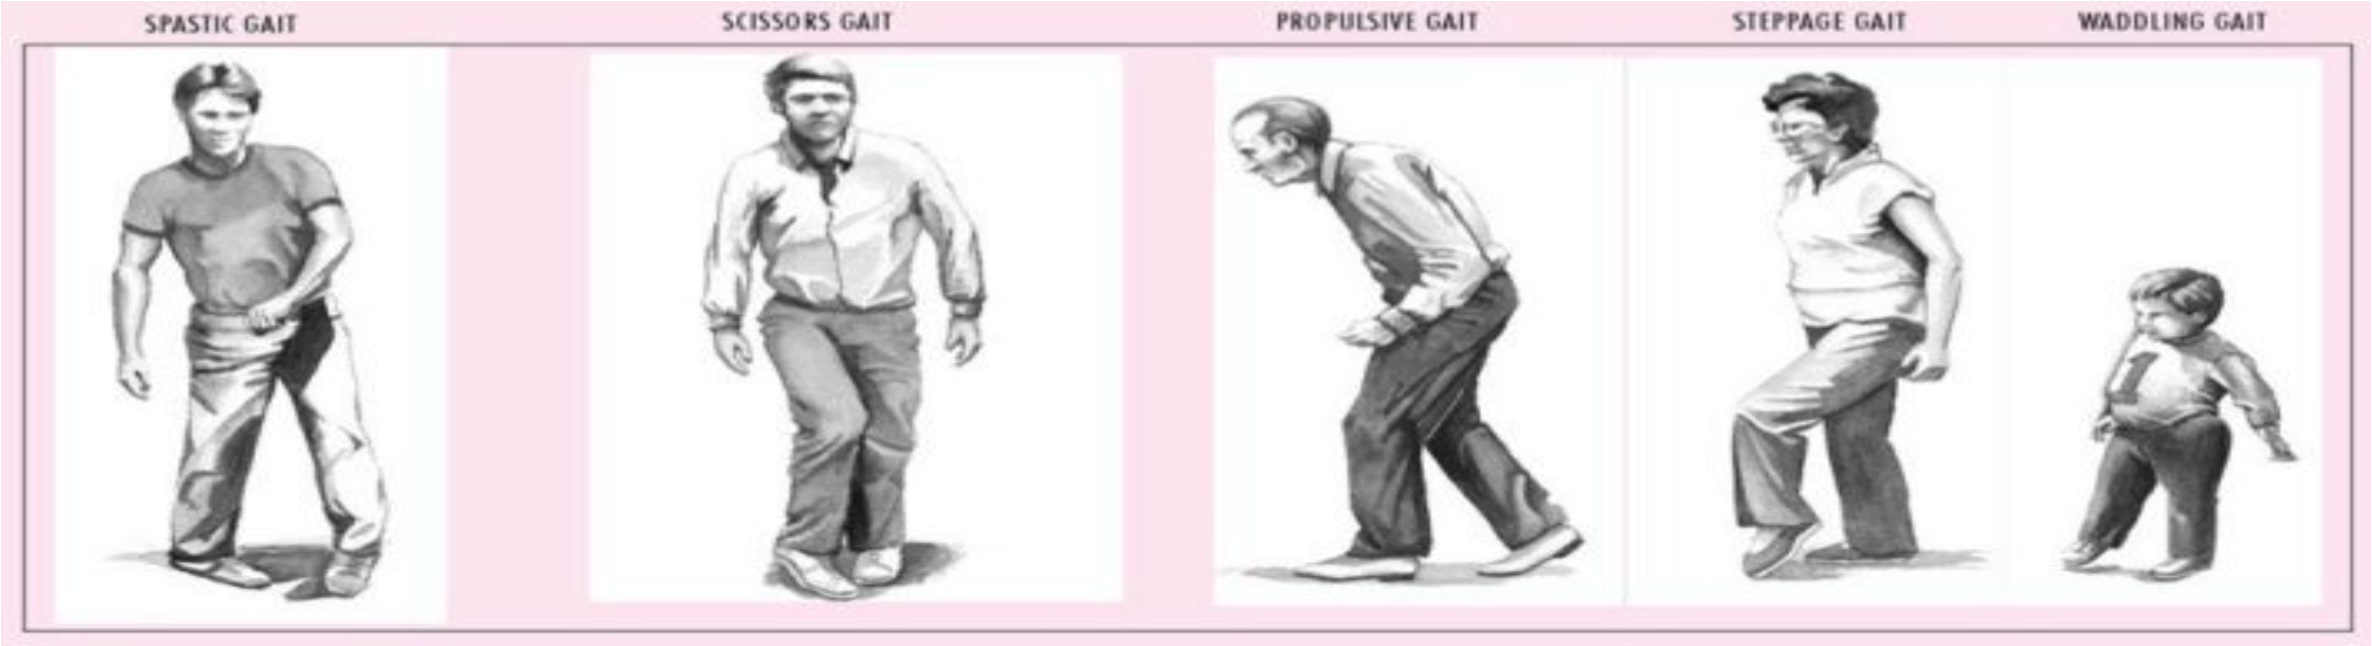

G) Gait

\The cerebellar examination is performed in patients with neurological signs or symptoms of cerebellar pathology, for example: dizziness, loss of balance, or poor co-ordination. There are many causes of cerebellar dysfunction and include vascular, for example: stroke, space-occupying lesions, multiple sclerosis, and genetic conditions such as Friedreich’s Ataxia.

The cerebellar examination needs to reflect these symptoms and as such involves examining the gait, balance and co-ordination.

Tandem gait: The examiner asks the patient to walk in a straight line with the heel of the leading foot touching the toes of the lagging foot as if walking on a tightrope.

| Gait Type | Description | Causes |

|---|---|---|

| Spastic Gait | Stiff, awkward movements with legs held close together and dragging feet. | - Cerebral palsy - Multiple sclerosis - Stroke - Spinal cord injury - Brain injury |

| Scissor Gait | Legs cross over each other while walking, resembling the motion of scissors. | - Cerebral palsy - Spinal cord injury - Multiple sclerosis - Spastic diplegia |

| Propulsive Gait | Stooped, rigid posture with small, shuffling steps, often leaning forward. | - Parkinson’s disease - Progressive supranuclear palsy - Basal ganglia disorders |

| Steppage Gait | High stepping, lifting the foot higher than usual to avoid dragging toes. | - Peripheral neuropathy - Foot drop (due to peroneal nerve injury) - Guillain-Barré syndrome |

| Waddling Gait | Swaying from side to side, often with a wide stance. | - Muscular dystrophy - Hip dysplasia - Myopathy - Congenital hip dislocation |

| Tandem Gait | Walking in a straight line, heel-to-toe, often used in neurological exams. | - Cerebellar ataxia - Alcohol intoxication - Vestibular disorders - Multiple sclerosis |

| Hemiplegic Gait | One leg is stiff and swings in a semicircle, with the arm on the same side flexed. | - Stroke - Traumatic brain injury - Cerebral palsy (hemiplegic type) - Multiple sclerosis |

| Spastic Hemiplegic Gait | Similar to hemiplegic gait but with increased muscle tone and stiffness. | - Stroke - Cerebral palsy (spastic hemiplegia) - Traumatic brain injury - Multiple sclerosis |